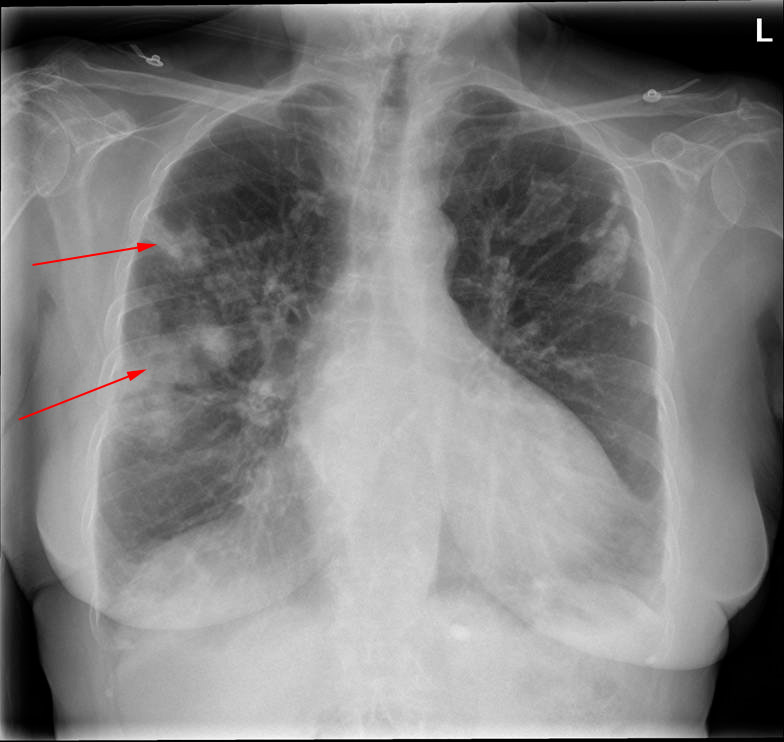

B: Et par uger efter første undersøgelse får patienten feber, og man foretager ny røntgenundersøgelse (B). Man ser, at der er kommet to infiltrater på højre side (røde pile); patienten har fået lungebetændelse.